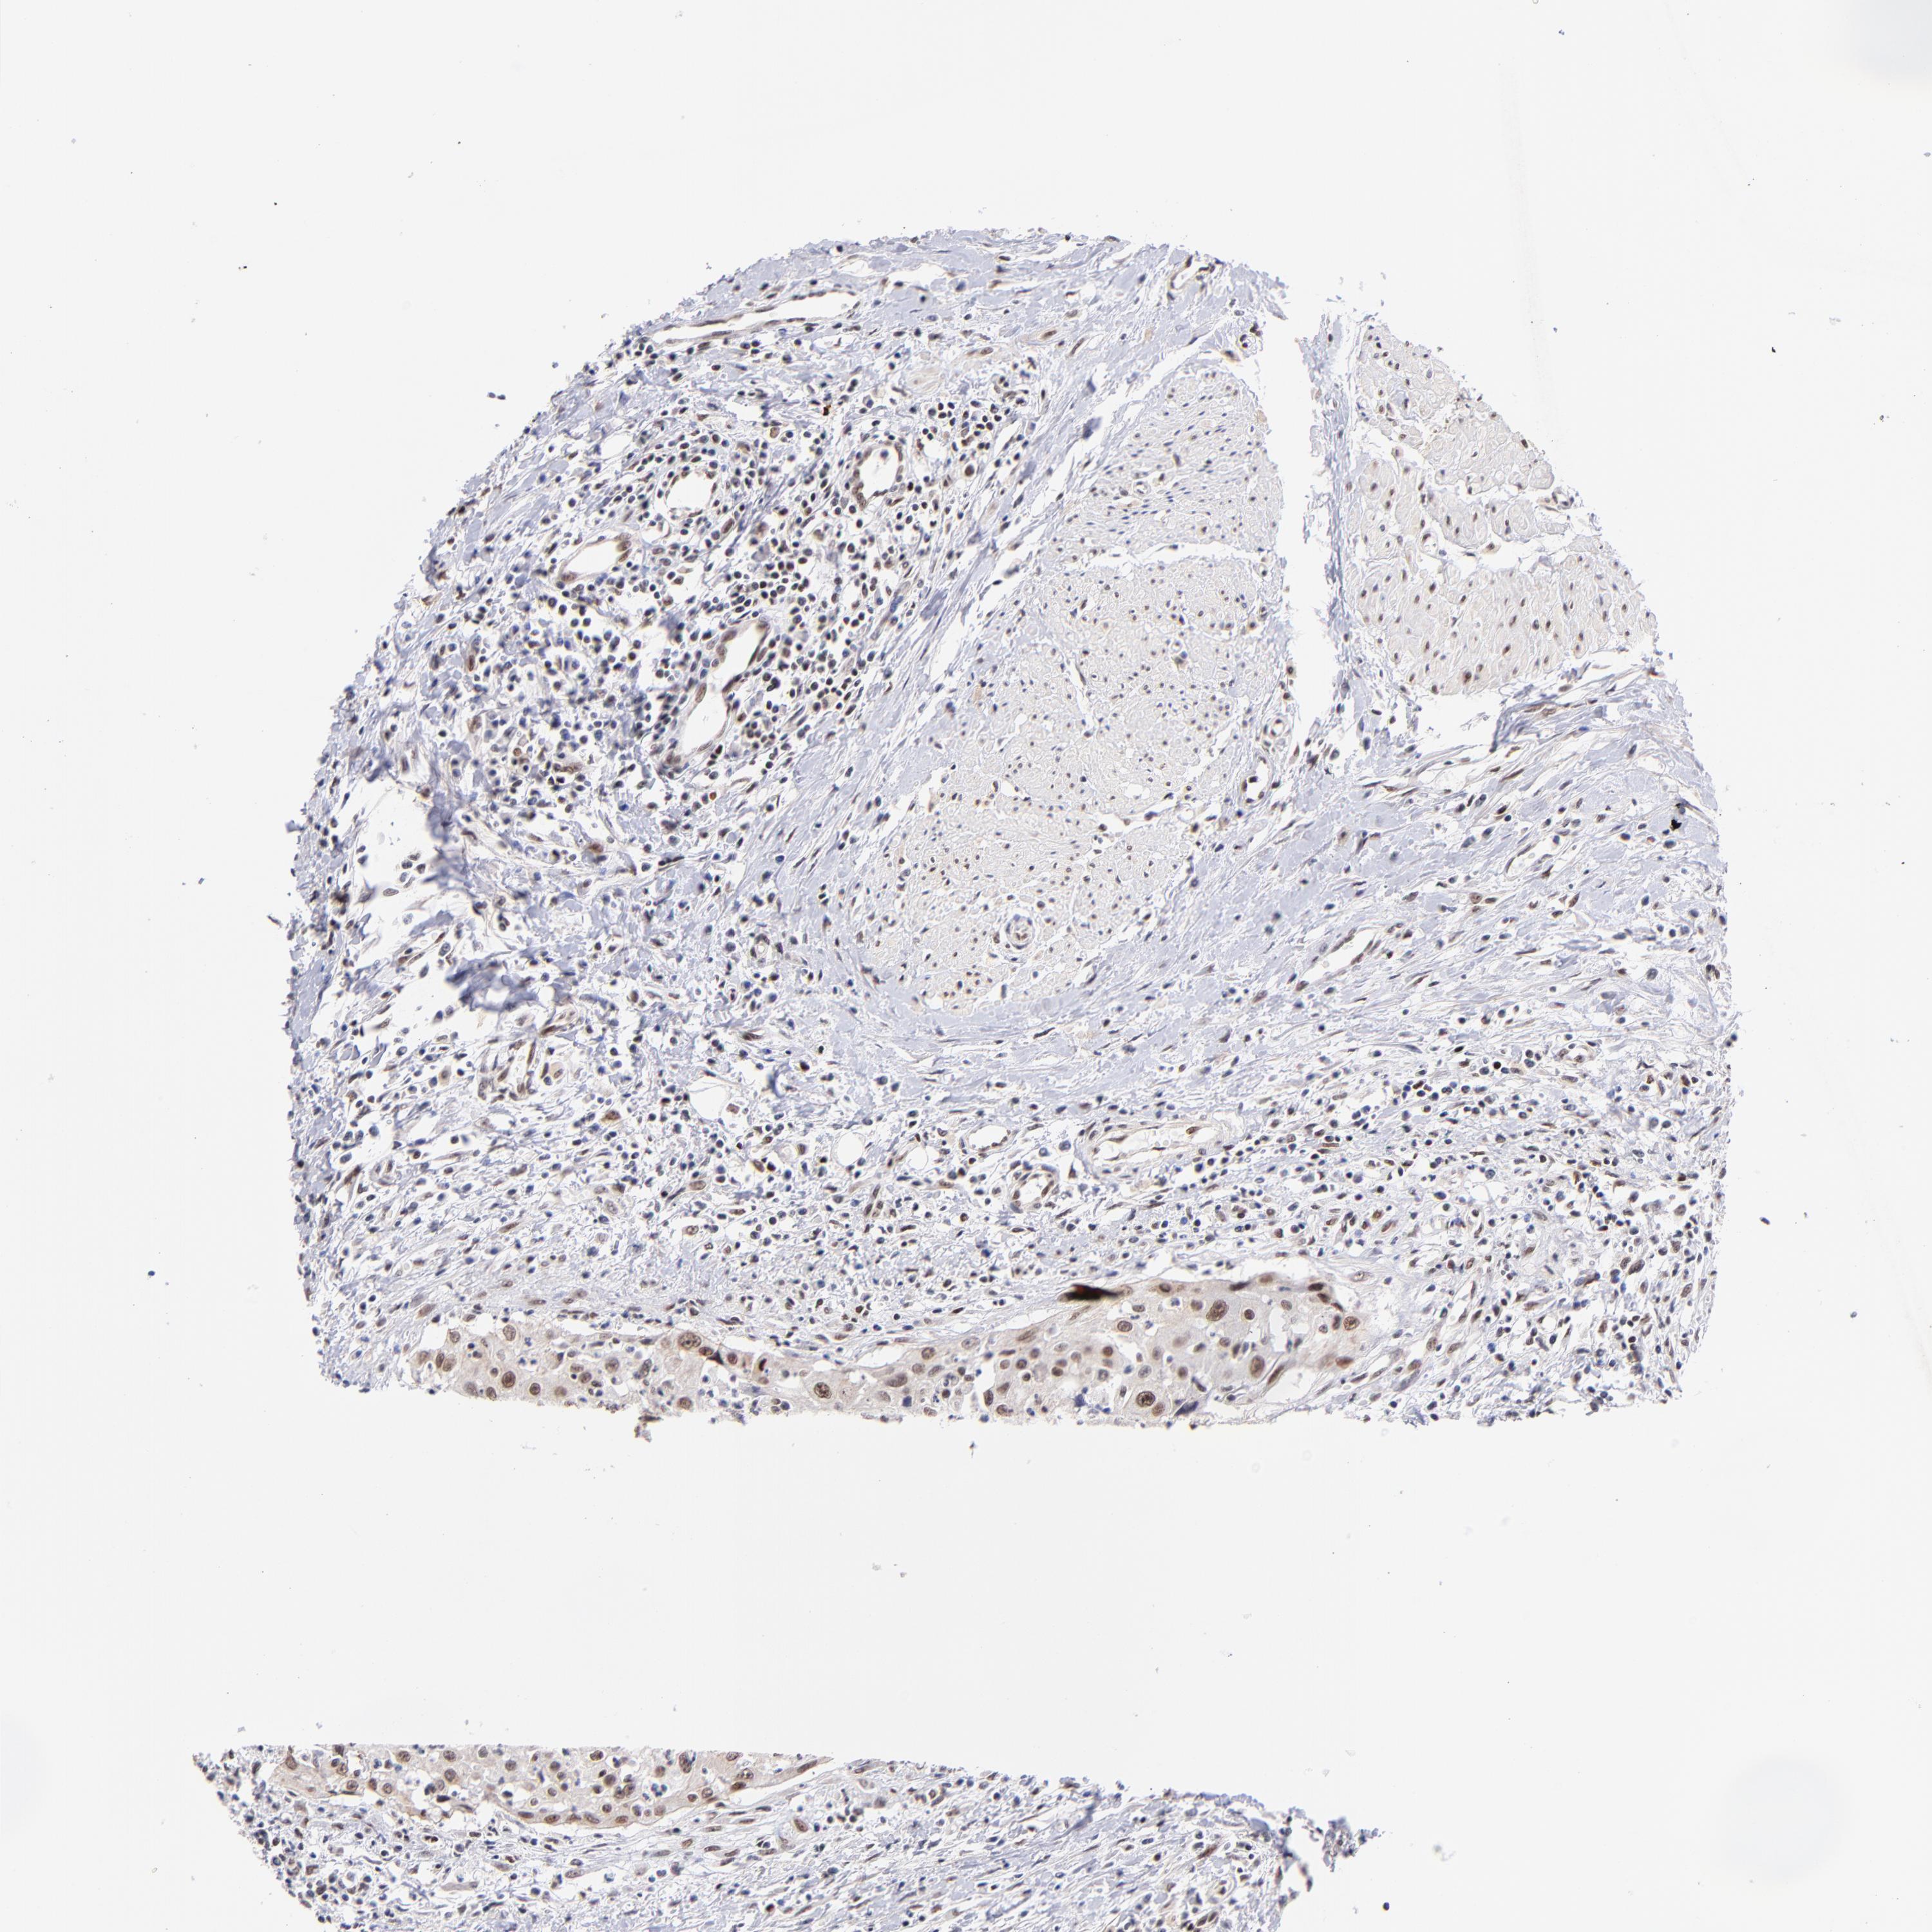

UROTHELIAL CANCER - Protein expressioni

A mouse-over function shows sample information and annotation data. Click on an image to view it in a full screen mode. Samples can be filtered based on level of antibody staining by selecting one or several of the following categories: high, medium, low and not detected. The assay and annotation is described here.

Note that samples used for immunohistochemistry by the Human Protein Atlas do not correspond to samples in the TCGA dataset.

Antibody stainingi

Antibody staining in the annotated cell types in the current human tissue is reported as not detected, low, medium, or high, based on conventional immunohistochemistry profiling in selected tissues. This score is based on the combination of the staining intensity and fraction of stained cells.

Each image is clickable and will lead to virtual microscopy that enables deeper exploration of all samples and also displays staining intensity scores, fraction scores and subcellular localization as well as patient and tissue information for each sample.

Antibody HPA003111

Staining

High

Medium

Low

Not detected

Intensity

Strong

Moderate

Weak

Negative

Quantity

>75%

75%-25%

<25%

None

Location

Nuclear

Cytoplasmic/membranous

Cytoplasmic/membranous,nuclear

Urothelial carcinoma, High grade

Urothelial carcinoma, Low grade